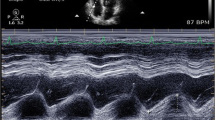

Echocardiographic data were obtained from a 1.5–3.6-MHz cardiac probe connected to a Vivid i echograph (GE Healthcare, Wauwatosa, WI, USA). To ensure consistency in the measurements of the echocardiographic indices, all TTE were performed by a limited number of physicians with advanced expertise in critical care echocardiography (R.B., X.R., or T.J.). Before the beginning of the inclusions, they all studied the latest recommendations of the American Society of Echocardiography endorsed by the European Association of Echocardiography [5] and performed several exams all together to harmonize their practices. ETT parameters were measured and calculated off-line on acquired images, blinded from the PAC values, on an average of 3 measurements.

The following RV systolic function parameters were measured as recommended by international guidelines [5]: fractional area change (FAC), tricuspid annular plane systolic excursion (TAPSE) in M-mode, and indices derived from the pulsed tissue Doppler at lateral tricuspid annulus—peak systolic velocity (S′), RV index of myocardial performance (RIMP), and isovolumic acceleration (IVA). RIMP is defined as the ratio of isovolumic time and ejection time; isovolumic time is calculated as the tricuspid opening time minus ejection time. Time interval is measured from a single beat. IVA is defined as the ratio of peak isovolumic myocardial velocity and time to peak velocity. The onset of myocardial acceleration is at the zero-crossing point of myocardial velocity during isovolumic contraction (Additional file 1).